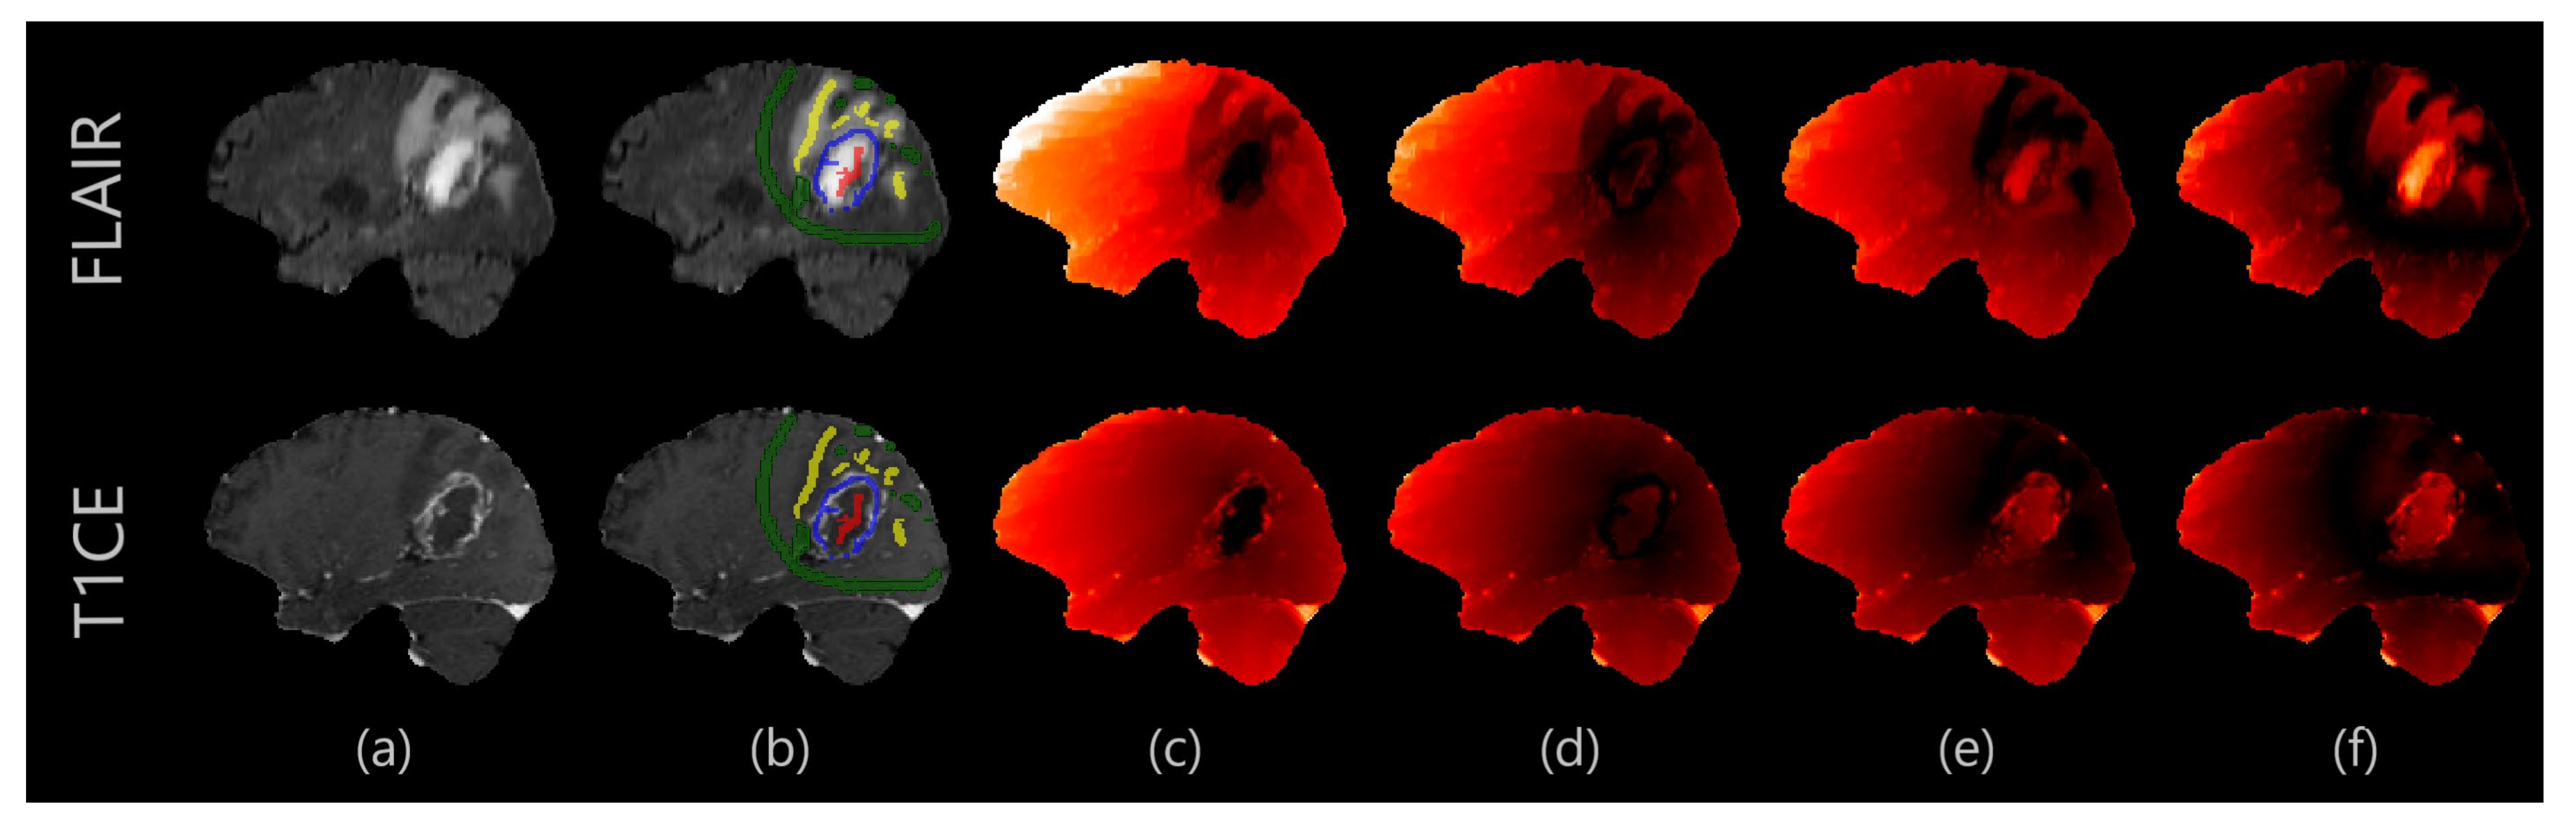

2.2. Proposed Segmentation Algorithm

3.1. Experiment 1: Overall Performance Evaluation